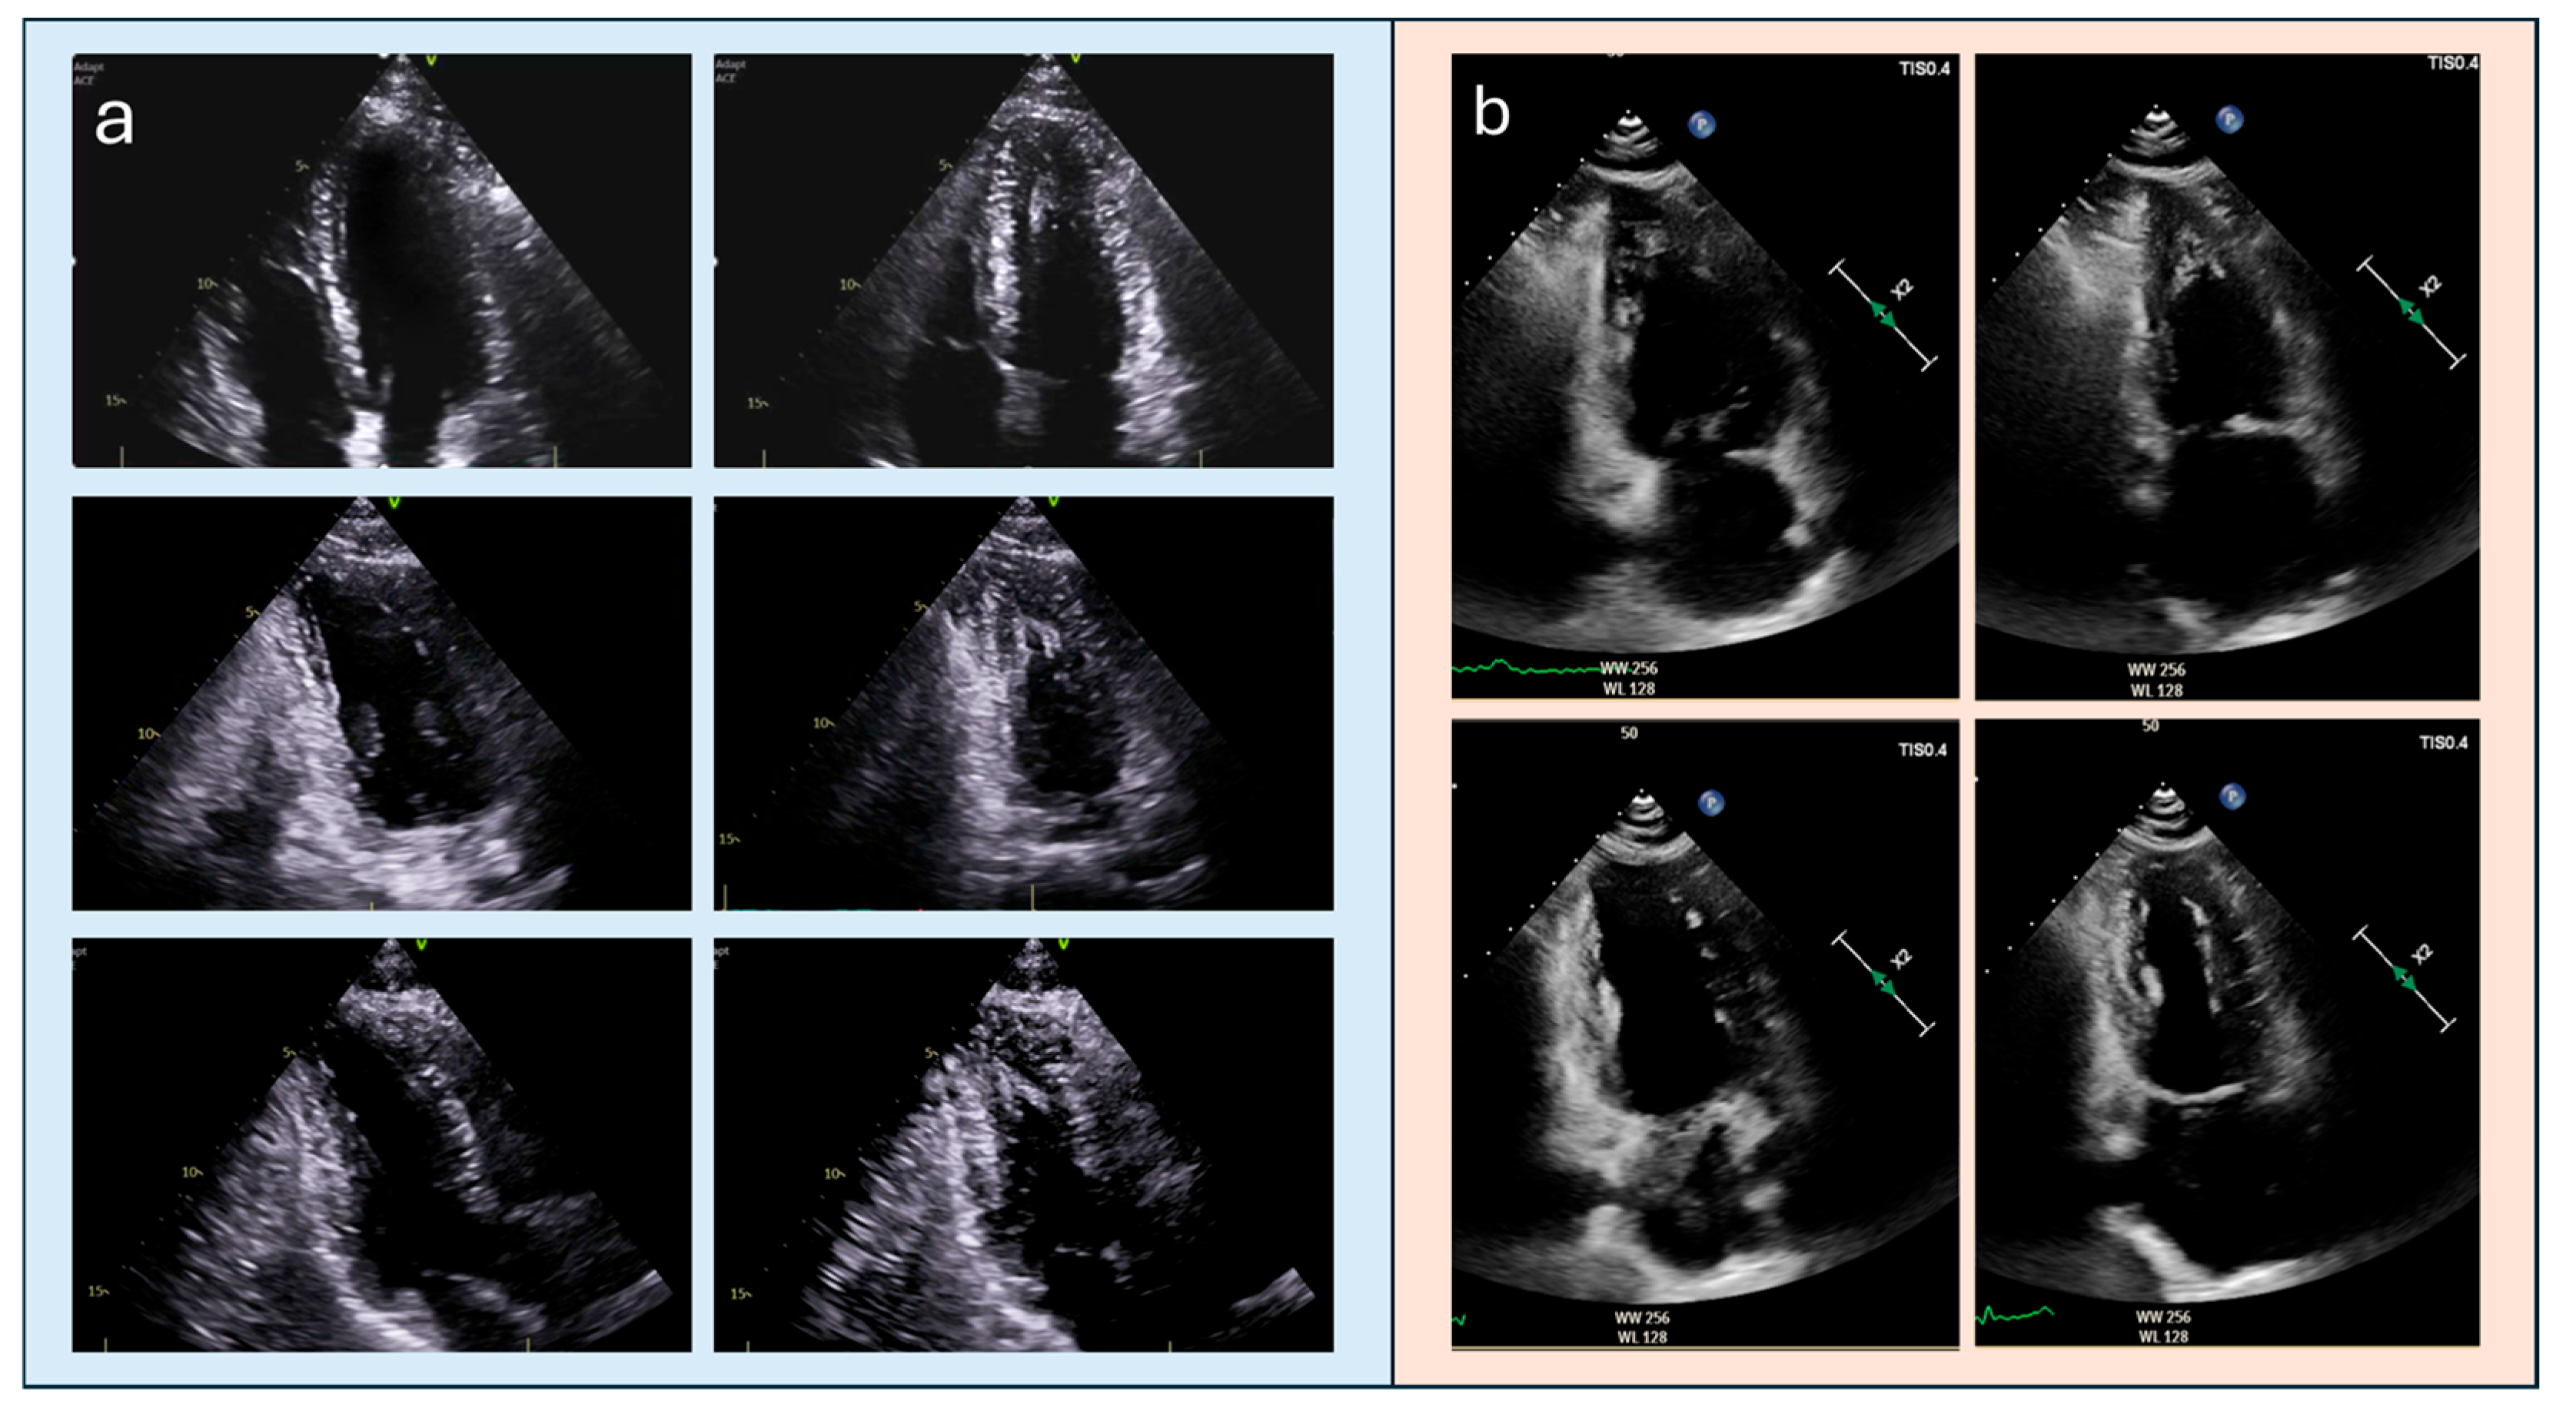

5. Differential Diagnosis and Interpretative Pitfalls

- Hamza, I.; Odigie-Okon, E.; Xie, T.; Ahmad, M. Apical Hypertrophic Cardiomyopathy: A Clinical & Multimodality Imaging Assessment. Echocardiography 2025, 42, e70235. [Google Scholar] [CrossRef]

- Porter, T.R.; Mulvagh, S.L.; Abdelmoneim, S.S.; Becher, H.; Belcik, J.T.; Bierig, M.; Choy, J.; Gaibazzi, N.; Gillam, L.D.; Janardhanan, R.; et al. Clinical Applications of Ultrasonic Enhancing Agents in Echocardiography: 2018 American Society of Echocardiography Guidelines Update. J. Am. Soc. Echocardiogr. 2018, 31, 241–274. [Google Scholar] [CrossRef] [PubMed]

- Porter, T.R.; Abdelmoneim, S.; Belcik, J.T.; McCulloch, M.L.; Mulvagh, S.L.; Olson, J.J.; Porcelli, C.; Tsutsui, J.M.; Wei, K. Guidelines for the cardiac sonographer in the performance of contrast echocardiography: A focused update from the American Society of Echocardiography. J. Am. Soc. Echocardiogr. 2014, 27, 797–810. [Google Scholar] [CrossRef] [PubMed]

- Hoffmann, R.; von Bardeleben, S.; Cate, F.T.; Borges, A.C.; Kasprzak, J.; Firschke, C.; Lafitte, S.; Al-Saadi, N.; Kuntz-Hehner, S.; Engelhardt, M.; et al. Assessment of systolic left ventricular function: A multi-centre comparison of cineventriculography, cardiac magnetic resonance imaging, unenhanced and contrast-enhanced echocardiography. Eur. Heart J. 2005, 26, 607–616. [Google Scholar] [CrossRef]